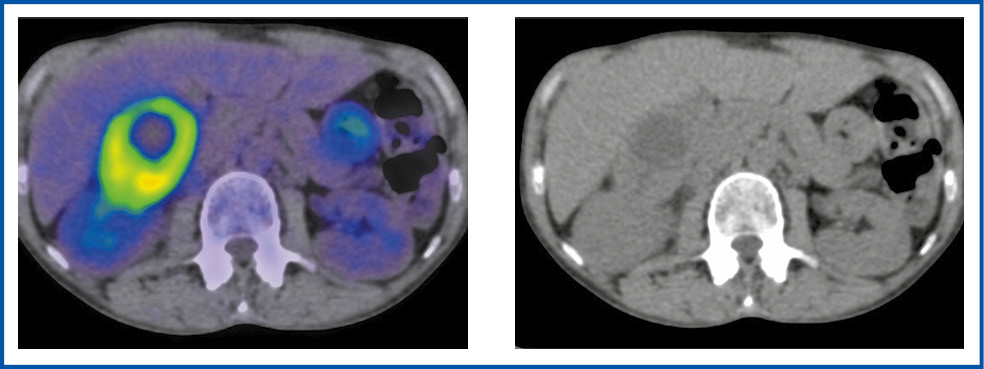

Неоднородную структуру опухоли наблюдали у 5 пациентов, кистозно-солидную – у 3, солидный характер образования – у 1 (рис. 1–4).

Рис. 2. Больной В., 63 года. В аксиальной проекции ПЭТ/КТ- и КТ-исследовании. В правом надпочечнике визуализируется многоузловое образование неоднородной структуры размером 88×70×72 мм с повышенной фиксацией РФП, SUVmax – 10,0.

Fig. 2. Patient V., 63 years old. Axial view of PET/CT and CT imaging: in the right adrenal gland, there is a multinodular mass with a heterogeneous structure, 88×70×72 mm with increased RPA uptake; SUVmax is 10.0.